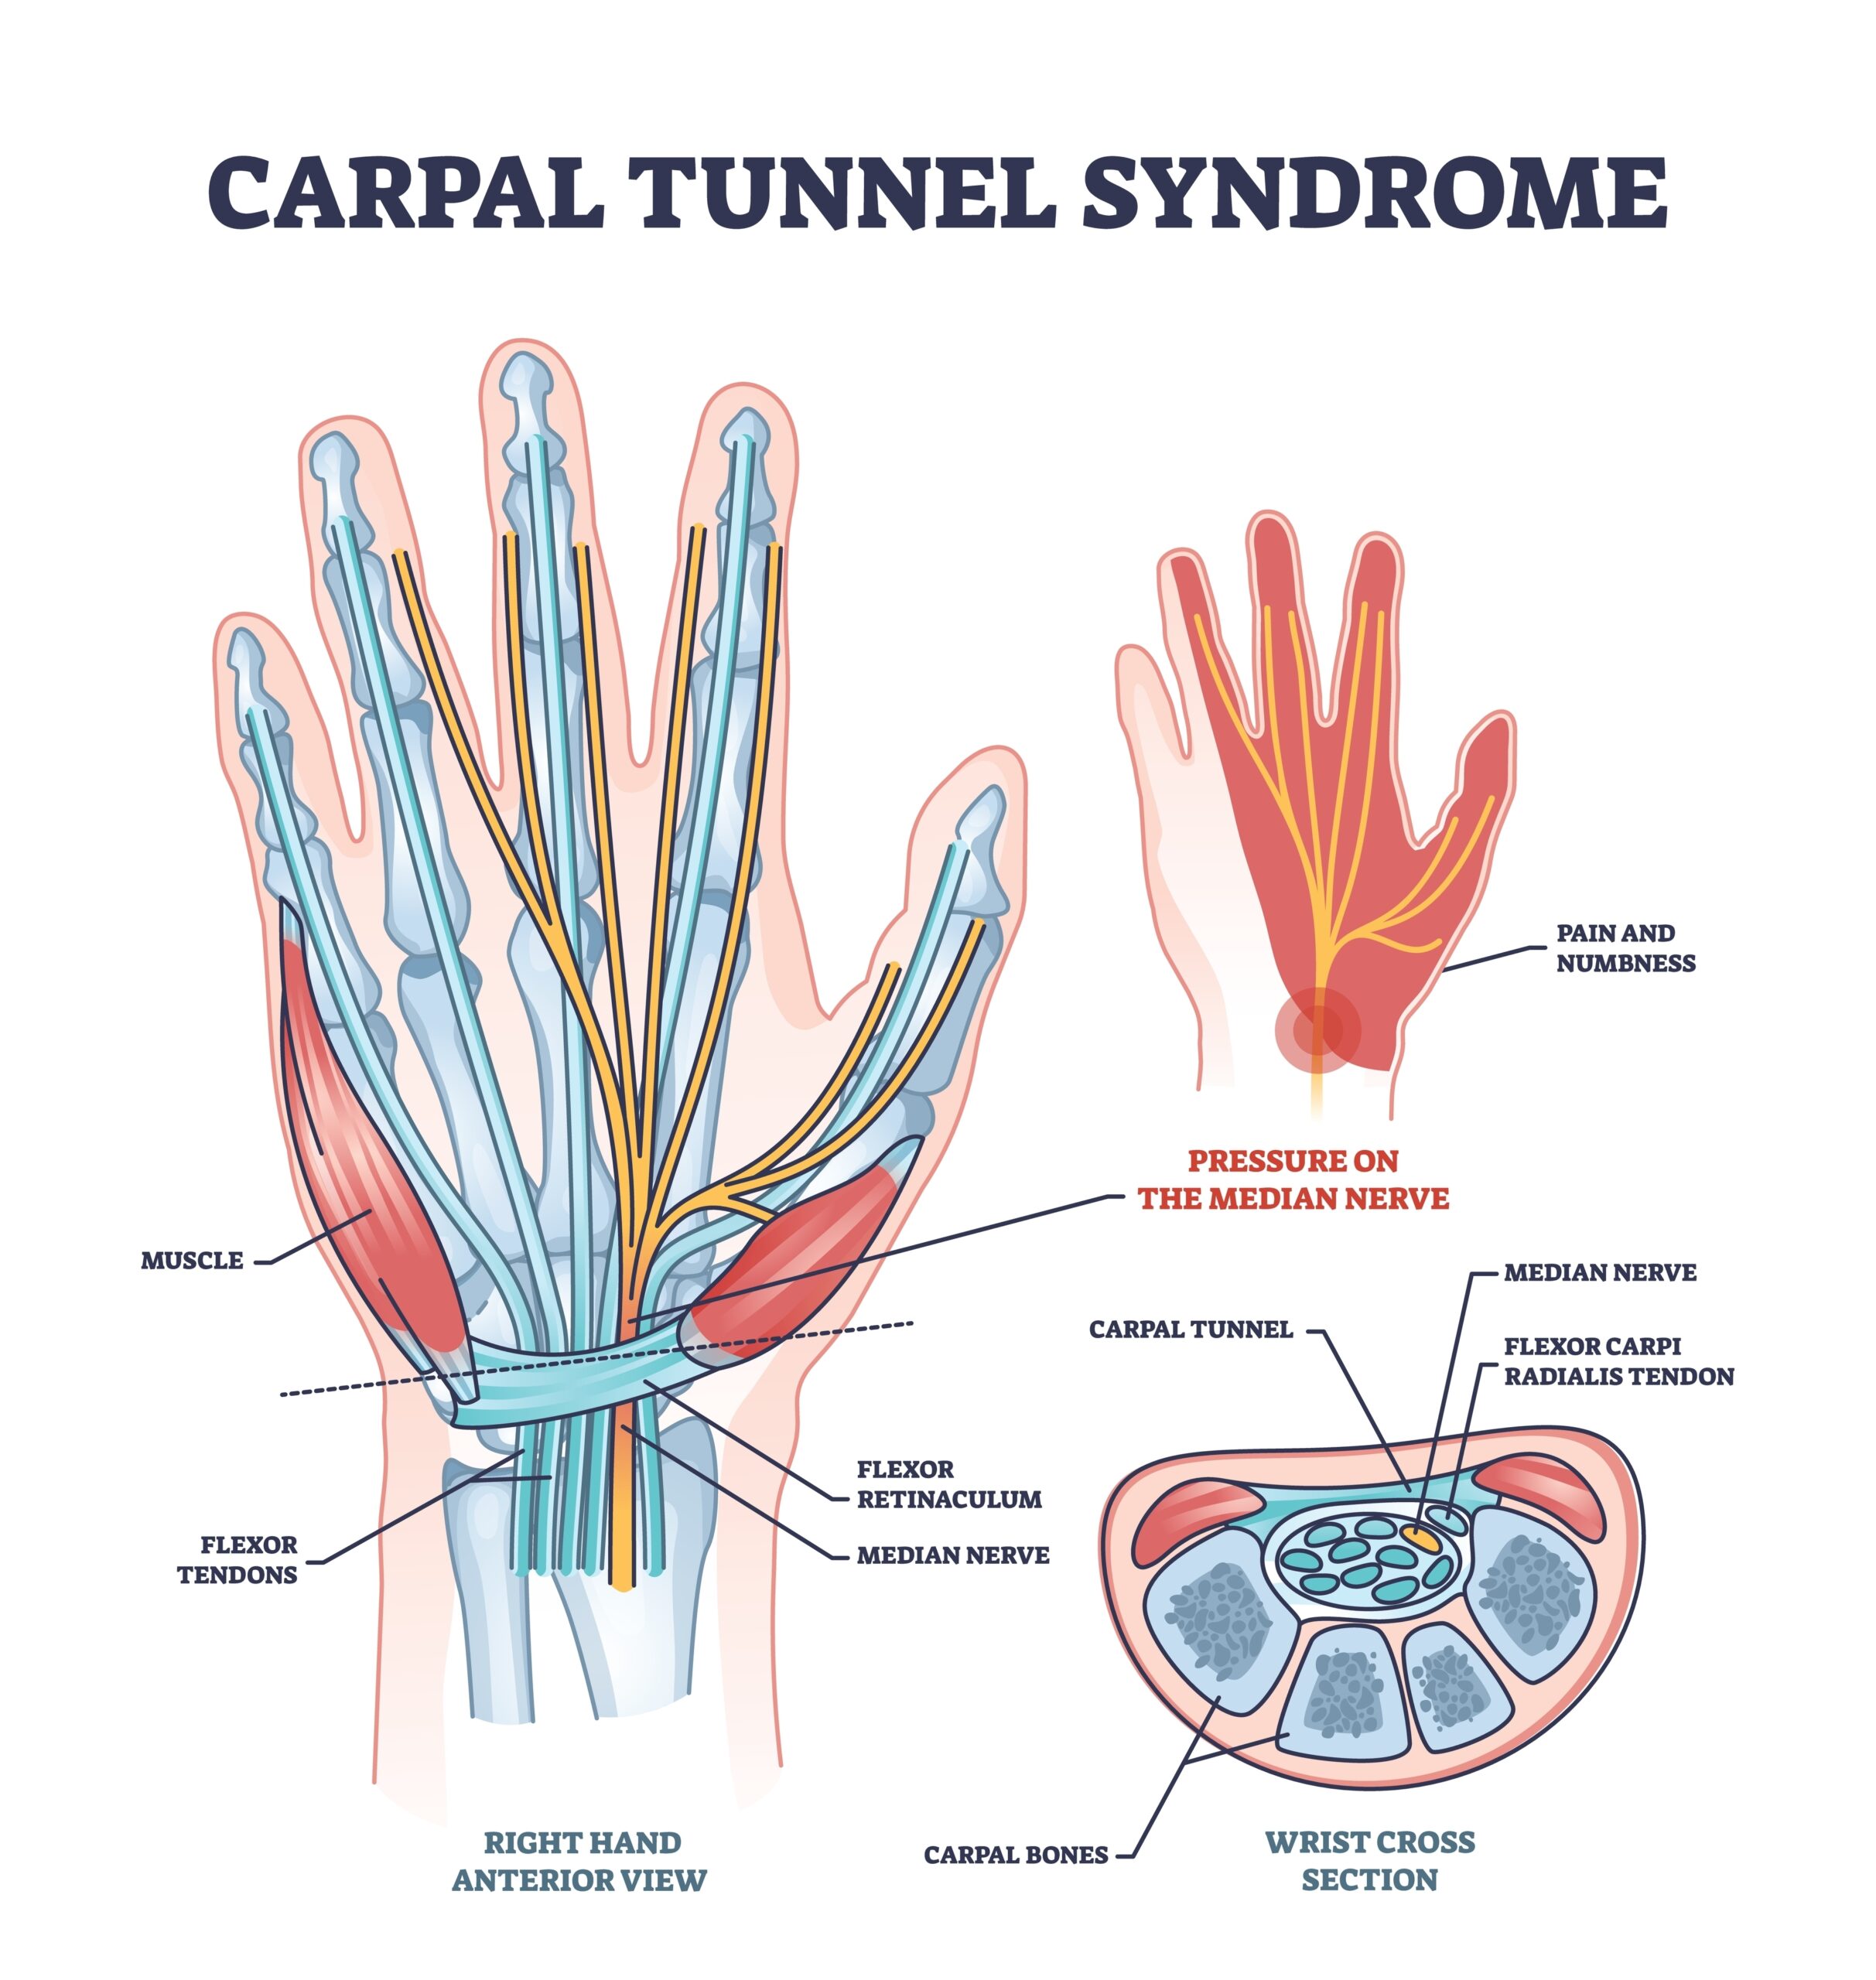

Carpal Tunnel Syndrome Treatment: Surgical vs. Hand Therapy Outcomes

Carpal Tunnel Syndrome Treatment: Surgical vs. Non-Surgical Outcomes Verdugo, R. J., Salinas, R. S., Castillo, J. L., & Cea, J. G. (2008). Surgical versus non-surgical treatment for carpal tunnel syndrome. ...

Carpal Tunnel Syndrome Treatment: Surgical vs. Hand Therapy Outcomes

Carpal Tunnel Syndrome Treatment: Surgical vs. Non-Surgical Outcomes Verdugo, R. J., Salinas, R. S., Castillo, J. L., & Cea, J. G. (2008). Surgical versus non-surgical ...

腕管松解术对双重挤压综合征和颈神经根病患者仍然有效

Hansen, LM, Jiang, EX, Hodson, NM, Livingston, N., Kazanjian, A., Wu, M., & Day, CS(2024)。有无双重挤压的患者...

糖尿病如何影响腕管手术结果

Preston Lake Moradi, A.、Sadr, A.、Ebrahimzadeh, MH、Hassankhani, GG 和 Mehrad-Majd, H. (2020) 撰写的文章评论。糖尿病会改变腕管功能吗?

腕管松解:儿科和青少年的结果

快速审查。基于病因学的儿童和青少年腕管松解的结果。 Velicki, K.、Goldfarb, CA、Roberts, S. 和 Wall, LB (2021)。 ...

手法治疗与手术治疗腕管综合症的有效性

Fernández-de-las-Peñas, C.、Cleland, J.、Palacios-Ceña, M.、Fuensalida-Novo, S.、Pareja, JA 和 Alonso-Blanco, C. (2017)。腕管手法治疗与手术治疗的有效性...

腕管综合症:传统手部疗法与神经动力学疗法相比如何?

Hamzeh, H.、Mohammad, M.、Alghwiri, A. 和 Hawamdeh, Z. (2021)。神经动力学与运动疗法对患有以下疾病的人的疼痛和功能的长期影响......

拔罐疗法作为腕管综合征理疗新方法的效果

文章审稿人:Rachel Reed Mohammadi, S.、Roostayi, MM、Naimi, SS 和 Baghban, AA (2019)。拔罐疗法的功效...

腕管症状的保守治疗:矫形器佩戴、动效贴和石蜡治疗效果的比较。

Kaplan, BM、Akyuz, G.、Kokar, S. 和 Yagci, I. (2018)。矫形干预、运动贴扎和石蜡治疗对患有以下疾病的患者的有效性比较